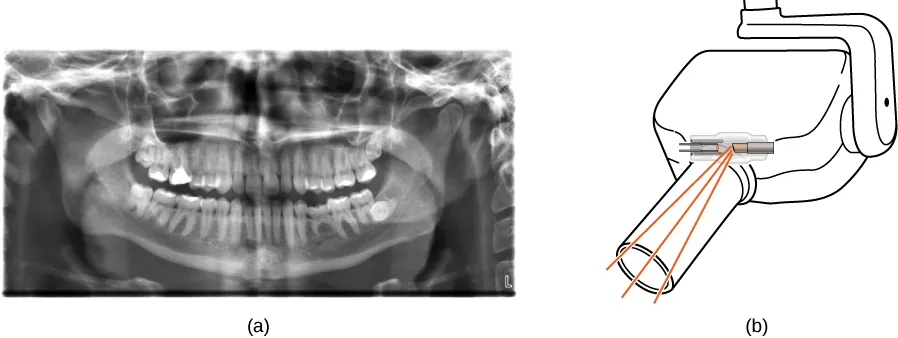

Technologia promieniowania rentgenowskiego

Promienie rentgenowskie mają wiele zastosowań związanych między innymi z diagnostyką medyczną (Ilustracja 8.25), kontrolą bagażu na lotniskach (Ilustracja 8.26), a nawet wykrywaniem pęknięć w istotnych dla bezpieczeństwa elementach samolotów. Najczęściej zdjęcia rentgenowskie przedstawiają cienie powstające w trakcie napromieniowania. Ponieważ fotony rentgenowskie mają dużą energię, przenikają przez substancje, które są nieprzezroczyste dla światła widzialnego. Im większą energię posiada foton, tym głębiej wnika w materiał. Głębokość penetracji jest związana zarówno z gęstością materiału, jak i energią fotonów. Im gęstszy materiał, tym mniej fotonów rentgenowskich go przenika i tym ciemniejszy jest cień. Promienie rentgenowskie są skuteczne w identyfikacji złamań kości i wykrywaniu nowotworów; jednak nadmierne naświetlanie promieniami rentgenowskimi może uszkadzać komórki organizmów biologicznych.

Figura (a) jest zdjęciem rentgenowskim szczęki ludzkiej. Figura (b) przedstawia aparat rentgenowski używany w gabinecie dentystycznym.

Ilustracja 8.25 (a) Zdjęcie rentgenowskie zębów pacjenta. (b) Typowy aparat rentgenowski w gabinecie dentystycznym, który wytwarza promieniowanie o stosunkowo małej intensywności w celu zminimalizowania stopnia naświetlania pacjenta. Źródło (a): modyfikacja pracy „Dmitry G”/Wikimedia Common